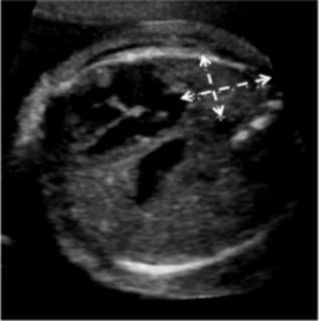

For each patient, the original ultrasound wherein the LHR had been calculated was reviewed, and the U/S LHR noted. A single reviewer (EP) analyzed these ultrasound images to determine the accuracy of of U/S LHR calculation. All practitioners in the Maternal Fetal Medicine department use the same technique for calculating LHR, the longest diameter method15. The images were reviewed to ensure that the cross-sectional area of the contralateral lung was measured at the four chamber view of the heart (Figure 1), the cross-sectional area was calculated with the longest diameter in the correct plane, the width was perpendicular in the correct plane, and the actual calculation was mathematically accurate. The U/S LHR values were then calculated by entering these measurements into the LHR calculator on perinatology.com. The inaccurate calculations were categorized based on the reason for inaccuracy: not measured at the level of the four chamber view of the heart, inaccurate calculation, poor images, no calipers, or oblique angle.

Figure 1.Fetal ultrasound demonstrating apropriate measurement of lung at the four-chamber view of the heart